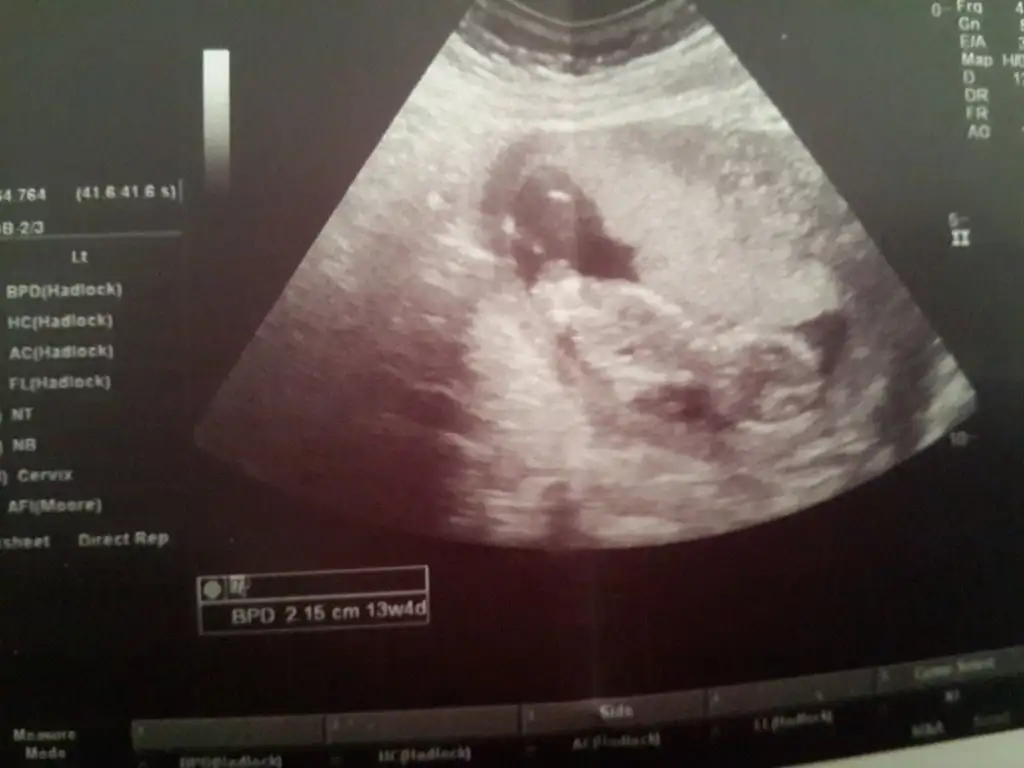

Slm kızlarrr bis geldik doktora gittik bugün fotomuzu aldık @msg38